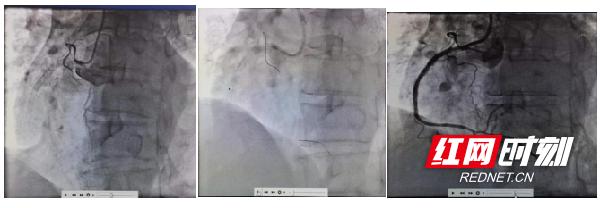

市中心医院冷水滩院区心血管内科主任龙双祁率冠脉介入团队仔细询问病史和阅读冠脉影像,详细讨论后认为患者支架内膜增生明显,若常规处理再狭窄率极高。故决定采用冠脉准分子激光斑块消融的方法,来解决患者冠状动脉病变。术中在冠状动脉内超声(IVUS)精确指导下,在右冠状动脉支架内反复行激光消蚀术2次后于右冠近中段顺序放入2枚药物球囊进行治疗,重新疏通了“心路”。患者术后观察了2天无不适症状,顺利出院。